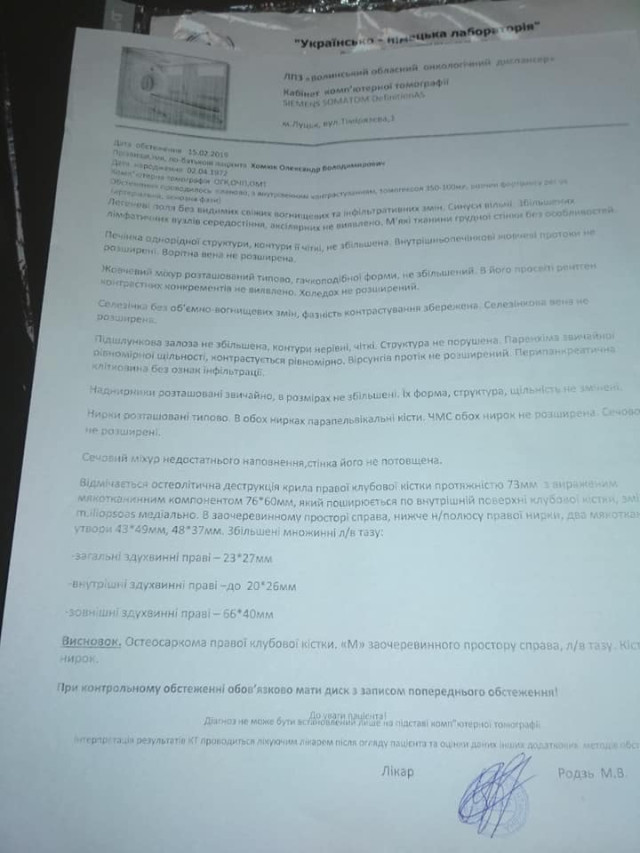

Як повідомили його близькі у Фейсбуці, у нього негоджкінська лімфома великих клітин В, початок 4 стадії.

Наприкінці листопада 2018 року росла гуля біля у пахві. Через три з половиною місяці вона збільшилась і як виявилося, це новоутвореня – злоякісна лімфома...

Як повідомили його близькі у Фейсбуці, у нього негоджкінська лімфома великих клітин В, початок 4 стадії.

Наприкінці листопада 2018 року росла гуля біля у пахві. Через три з половиною місяці вона збільшилась і як виявилося, це новоутвореня – злоякісна лімфома...